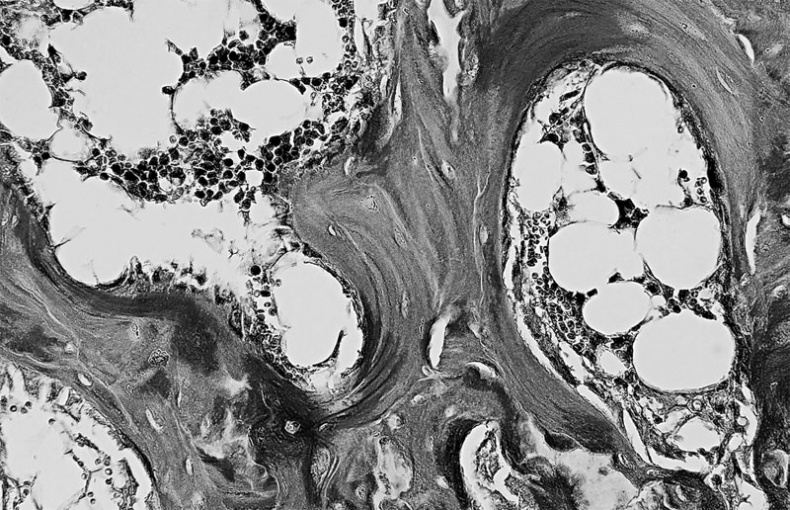

Особенность третья — костная ткань имеет пластинчатое строение. Каждая пластинка представляет собой тонкий пучок параллельно расположенных коллагеновых волокон, между которыми находятся остеоциты и аморфное вещество, содержащее кристаллы минеральных солей. Волокна соседних пластинок располагаются под углом друг к другу, часть их переходит из одной пластинки в другую, что обуславливает их плотное соединение, а, следовательно, и высокую прочность костей. Пластинок, располагаются вокруг каналов, в которых проходят кровеносные сосуды и нервы, образуя многослойные концентрические цилиндры.

Костные пластинки, образующие канал для кровеносного сосуда (в центре)

Под компактным веществом располагается губчатое вещество — костная ткань ячеистого вида, сформированная рыхло лежащими костными перекладинами. В ячейках, образованных этими перекладинами находится красный костный мозг, орган кроветворения. Благодаря своей рыхлой структуре, губчатое вещество легче компактного веществом, но уступает ему в прочности.